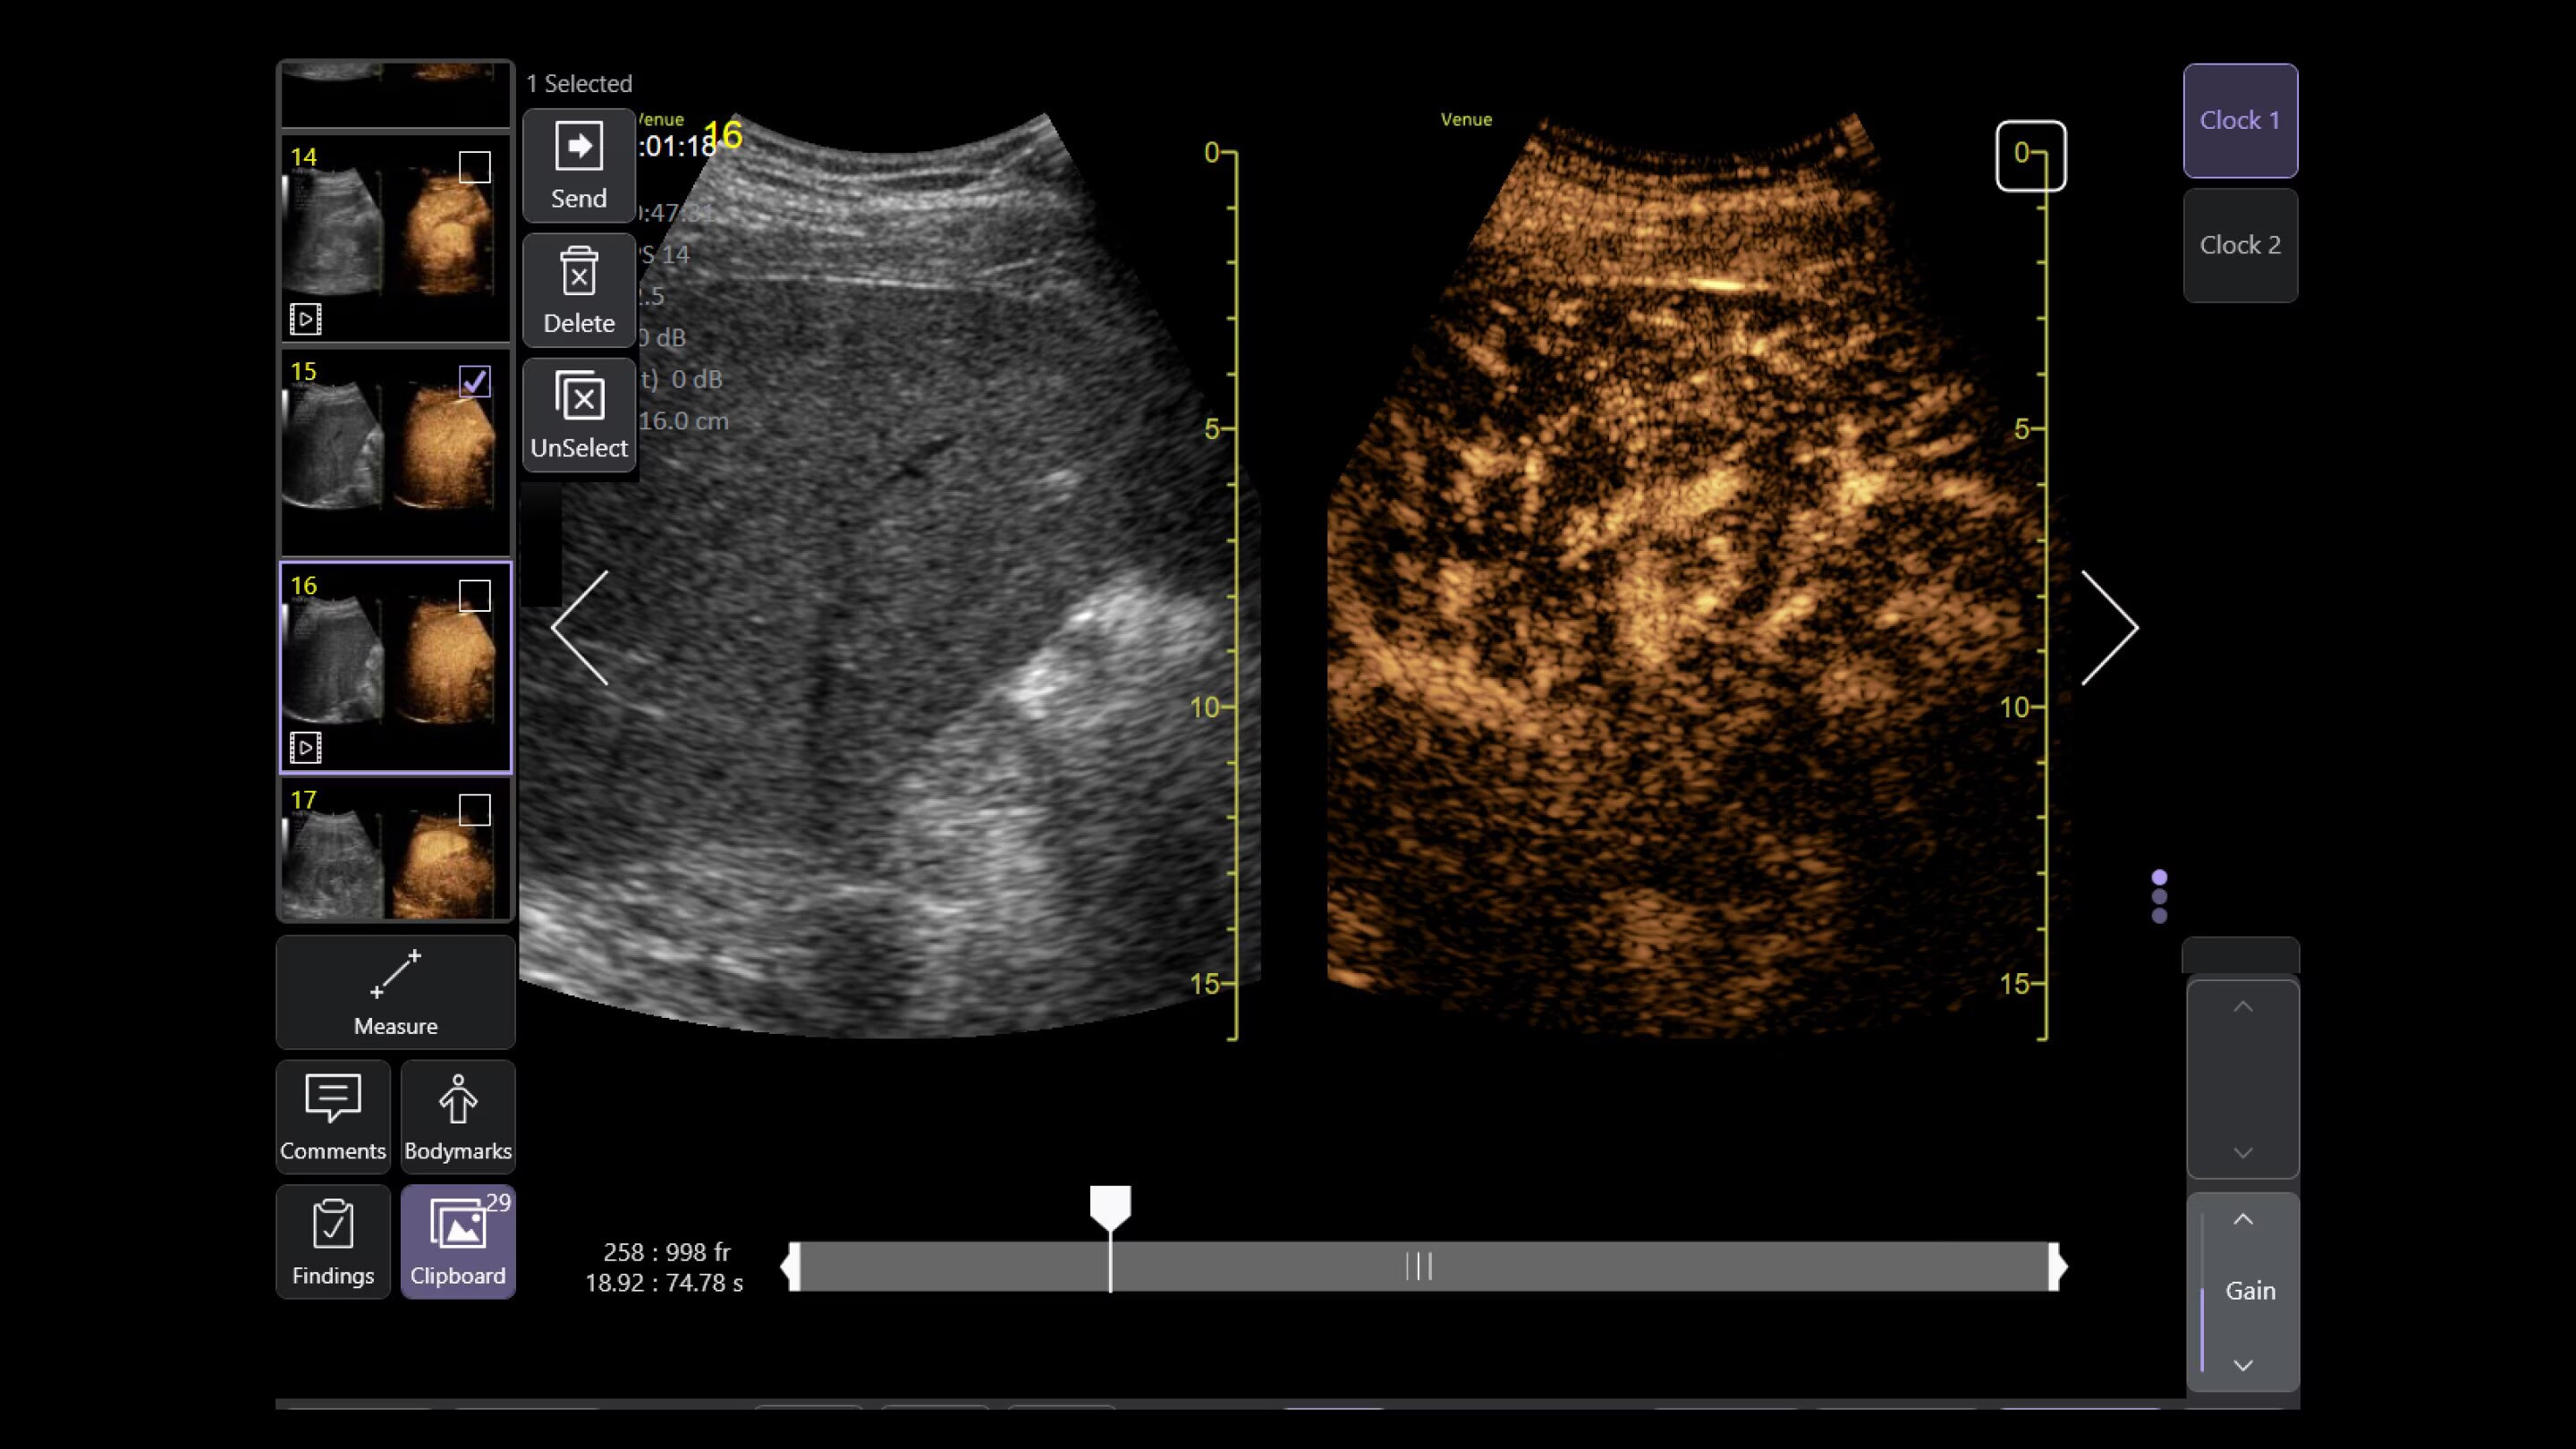

Automated tools

Simplify your workflow with AI-enabled clinical tools.

Helping drive consistency from user to user (whether one is an ultrasound novice or expert), Venue Fit features AI-enabled resources that help clinicians work smarter and more efficiently. Utilizing proprietary algorithms, we synthesize data from numerous patients to ensure accurate calculations for clinical confidence.